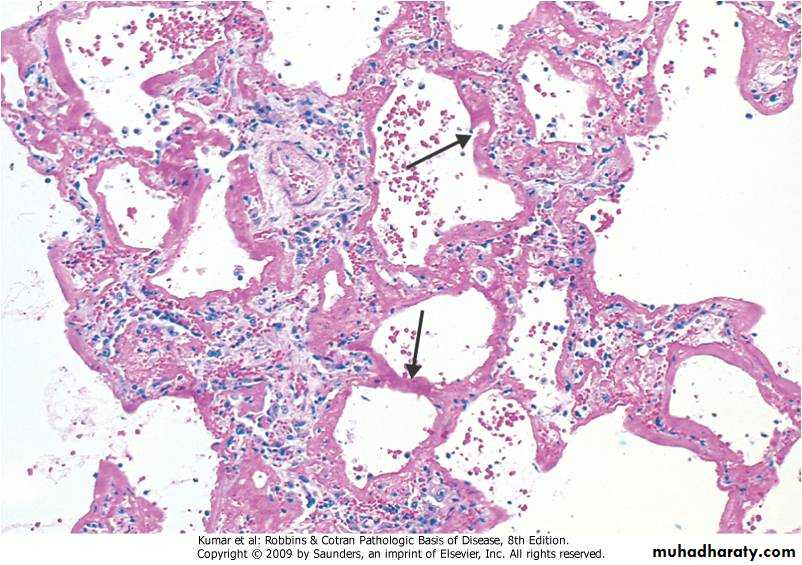

3 ,Adenocarcinoma : Arises from mucus gland in the bronchial mucosa, Consist of malignant glands with mucus secretion

4.Broncho alveolar carcinoma: A form of adenocarcinoma arises from terminal bronchoalveolar region It grows on preexisting structure (alveolar wall) without its destruction

Adenocarcinoma -Bronchus

Respiratory  System

Bronchoalveolar carcinoma